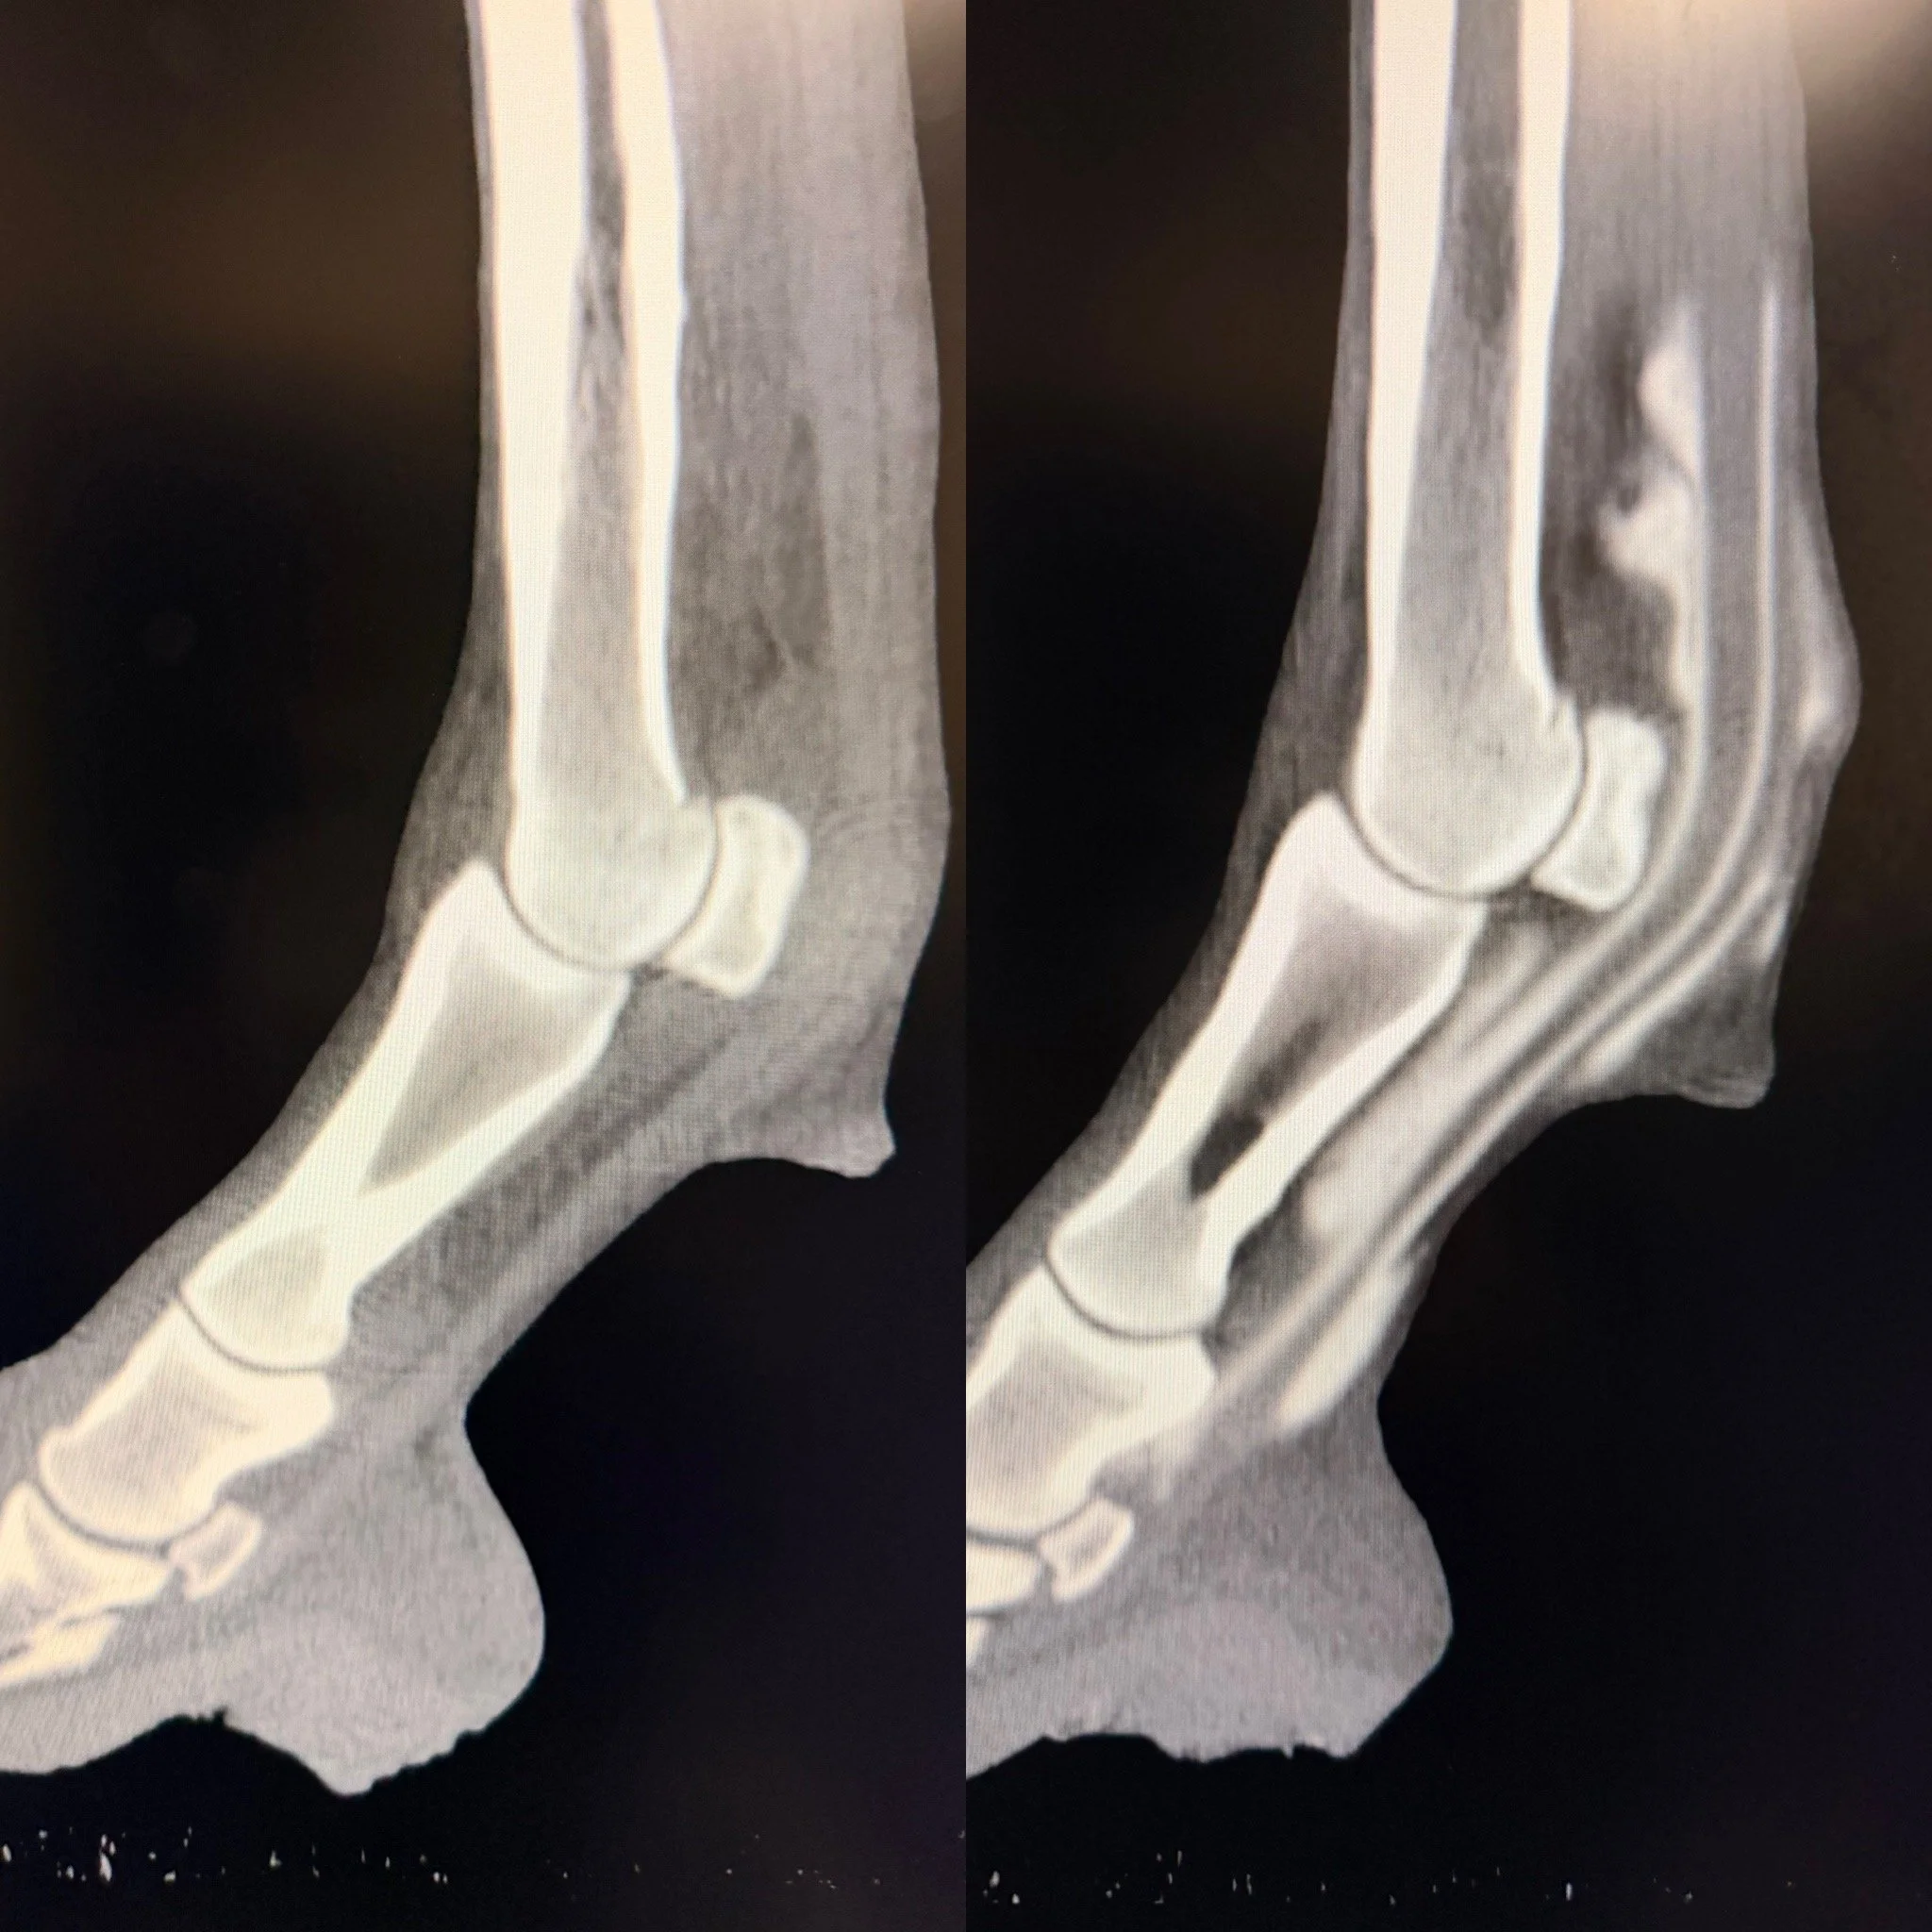

X-ray images of a human ankle and foot, showing the bones and joints in side and front views.

CT scan of a human ankle in lateral view, with cross-sectional images of the ankle's bones from above and below.